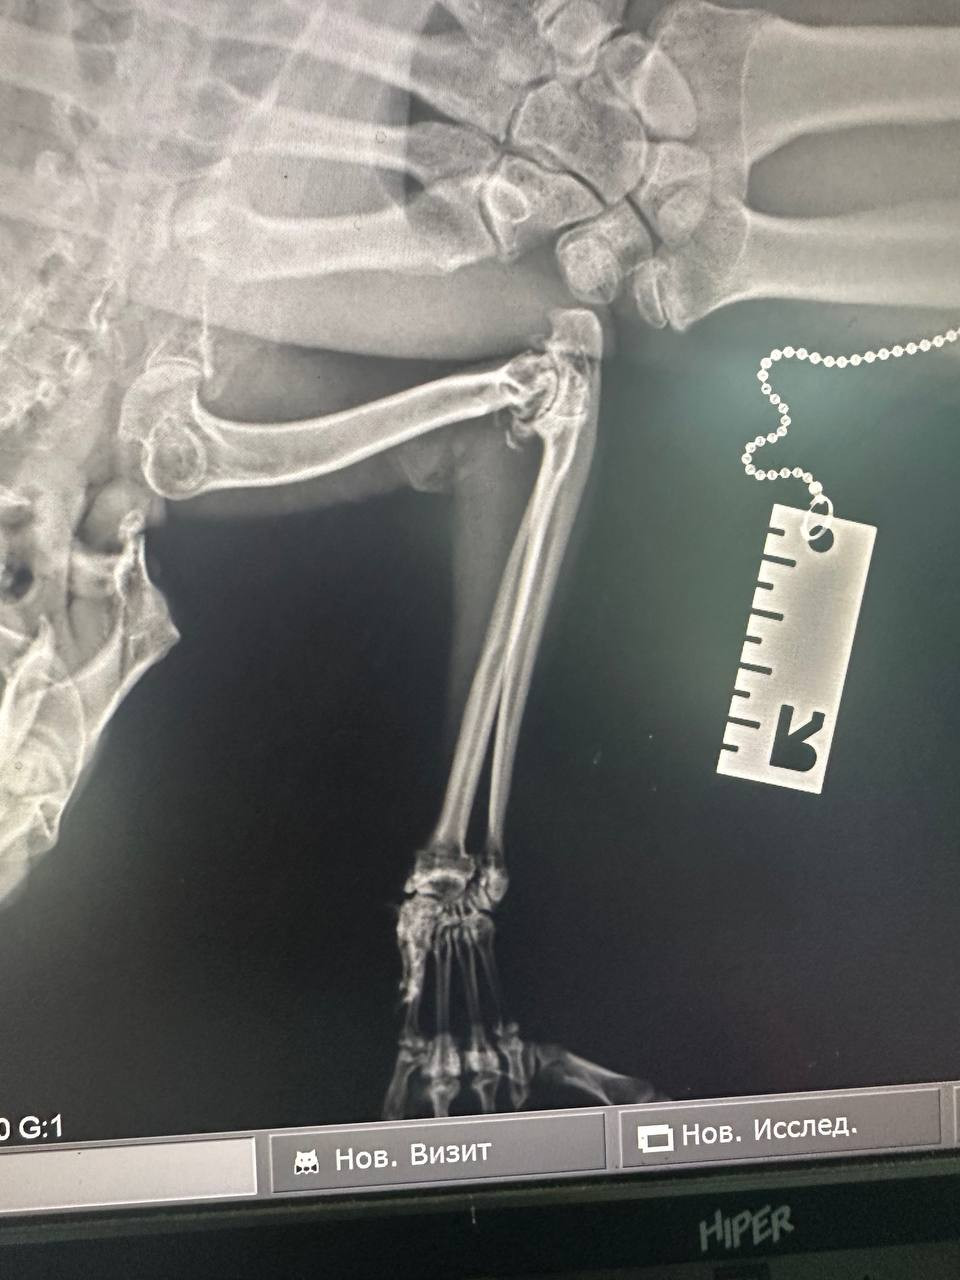

Сегодня отвезли уже в больницу, сделали рентген, врач поставил диагноз Воспаление кости, назначил антибиотик и сказал прогноз неизвестен, но по его интонации, как будто не очень хороший. Коту 13 лет . Шотландский вислоухий .

Я вас прикреплю снимки рентгена, можете пожалуйста оценить своим профессиональным взглядом соответствует ли поставленный диагноз действительно? Или на что это вообще похоже? Помогите  пожалуйста, очень сильно переживаем

Здравствуйте. По рентгеновскому снимку видно выраженное изменение структуры кости предплечья это участки разрежения, неровности кортикального слоя, что действительно может соответствовать остеомиелиту (воспалению кости). Диагноз, поставленный врачом, обоснован. Учитывая возраст и наличие артроза, течение может быть затяжным, но при правильной антибиотикотерапии и поддержке прогноз может быть осторожно благоприятным.

Здравствуйте. Снимок показывает патологические изменения в кости, вероятно, воспалительного характера (остеомиелит). Важно уточнить, нет ли скрытой травмы или опухолевого процесса, которые тоже могут давать такую картину. Назначение антибиотика это верный шаг, но для прогноза имеет значение общее состояние, ответ на лечение и контрольные снимки через 2-3 недели. Рекомендую наблюдение у ветеринара с опытом в ортопедии.